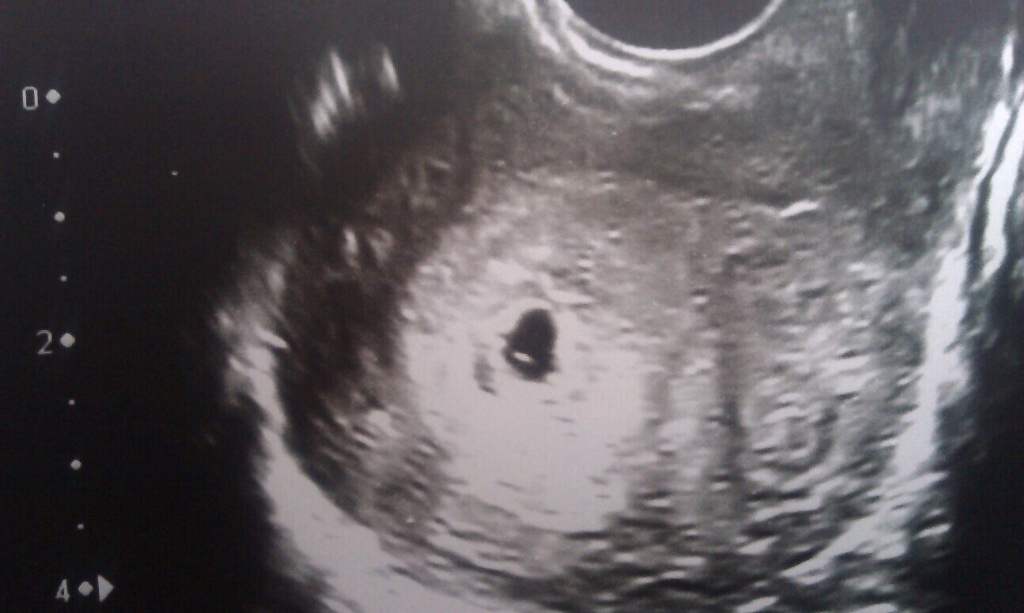

Приходит пациентка, допустим, с нерегулярным циклом, и первое ультразвуковое исследование говорит о том, что у неё анэмбриония, или неразвивающаяся беременность, что не соответствует действительности, потому что при выдаче такого рода заключения часть специалистов не учитывают, что, допустим, у пациентки цикл не 28 дней, среднестатистический, а короче или длиннее, чаще всего длиннее. Овуляция зачастую совершенно непредсказуема, она может произойти раньше или позже даже у женщин с совершенно, абсолютно регулярным циклом. Плюс, погрешность ультразвука в определении срока, в ранние сроки, до 8 недели, составляет около 5 дней. Сердцебиение, которое говорит о жизнеспособности плода, которое ультразвуковисты зачастую не видят в ранние сроки, появляется где-то на 37-ой день гестации.

Для выполнения УЗИ на раннем сроке должны быть показания. Основная цель —установить маточную локализацию плодного яйца: маточная, внематочная; вторая цель — определить жизнеспособность плодного яйца. Анатомия и все остальное — уже ближе к первому скринингу в 11-14 недель, но УЗИ в ранние сроки в основном преследуют эти две цели. По определенным ультразвуковым параметрам их возможно сделать.